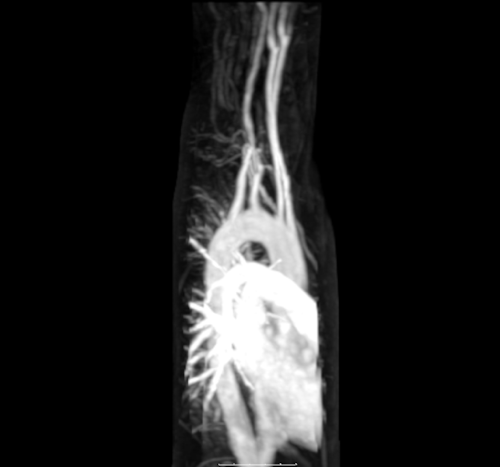

Home Anatomy Cardiopulmonary Blood Vessels 9 years ago 9 years ago Anatomy, Cardiology, Radiology Cardiopulmonary Blood Vessels by samer176 9 years ago9 years ago 104views [zombify_post] Post PaginationPrevious PostPreviousNext PostNext gif, heart, lung, vessels